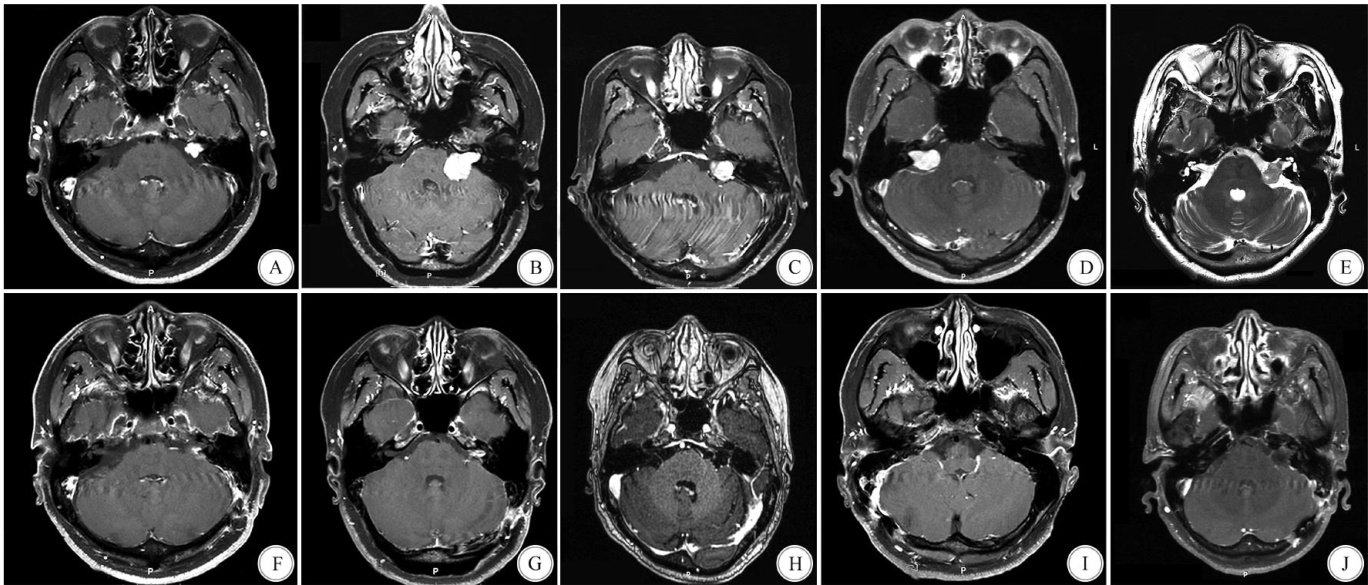

Abstract: ObjectiveTo explore the clinical application value of the Chameleon endoscope combined with the“three-piece set for internal auditory canal(IAC)” in clearing residual tumors in the IAC during microsurgical resection of acoustic neuroma.MethodsThe clinical data of 5 patients who underwent microsurgical resection of acoustic neuroma with residual IAC tumors, treated by the Chameleon endoscope combined with the“three-piece set for IAC” in the Department of Neurosurgery,the First Afiliated Hospital of Chongqing Medical University from August 2023 to June 2024,were analyzed retrospectively. The relevant literature were summarized and reviewed. ResultsGross total resection of tumors was achieved in all 5 patients.One patient retained functional hearing,one suffred from hearing loss(tumor diameter:approximately 3 cm),and the other three maintained preoperative hearing levels. At 6 months postoperatively, the HouseBrackmann(H-B) facial nerve function grade was II in 1 patient and I in the remaining 4 patients. Postoperative intracranial infection occurred in 1 patient,with no other complications. Conclusions The Chameleon endoscope can effectively expose the entire IAC. Combined with the“three-piece set for IAC”,it allows for complete clearance of residual tumors at the narrow fundus of the IAC, serving as a reliable technical guarantee for preserving facial nerve function and hearing.

听神经瘤亦称前庭神经鞘瘤,约占脑桥小脑角(cerebellopontineangle,CPA)肿瘤的 80% 、颅内肿瘤的 6%~9%[1] 。(剩余9076字)